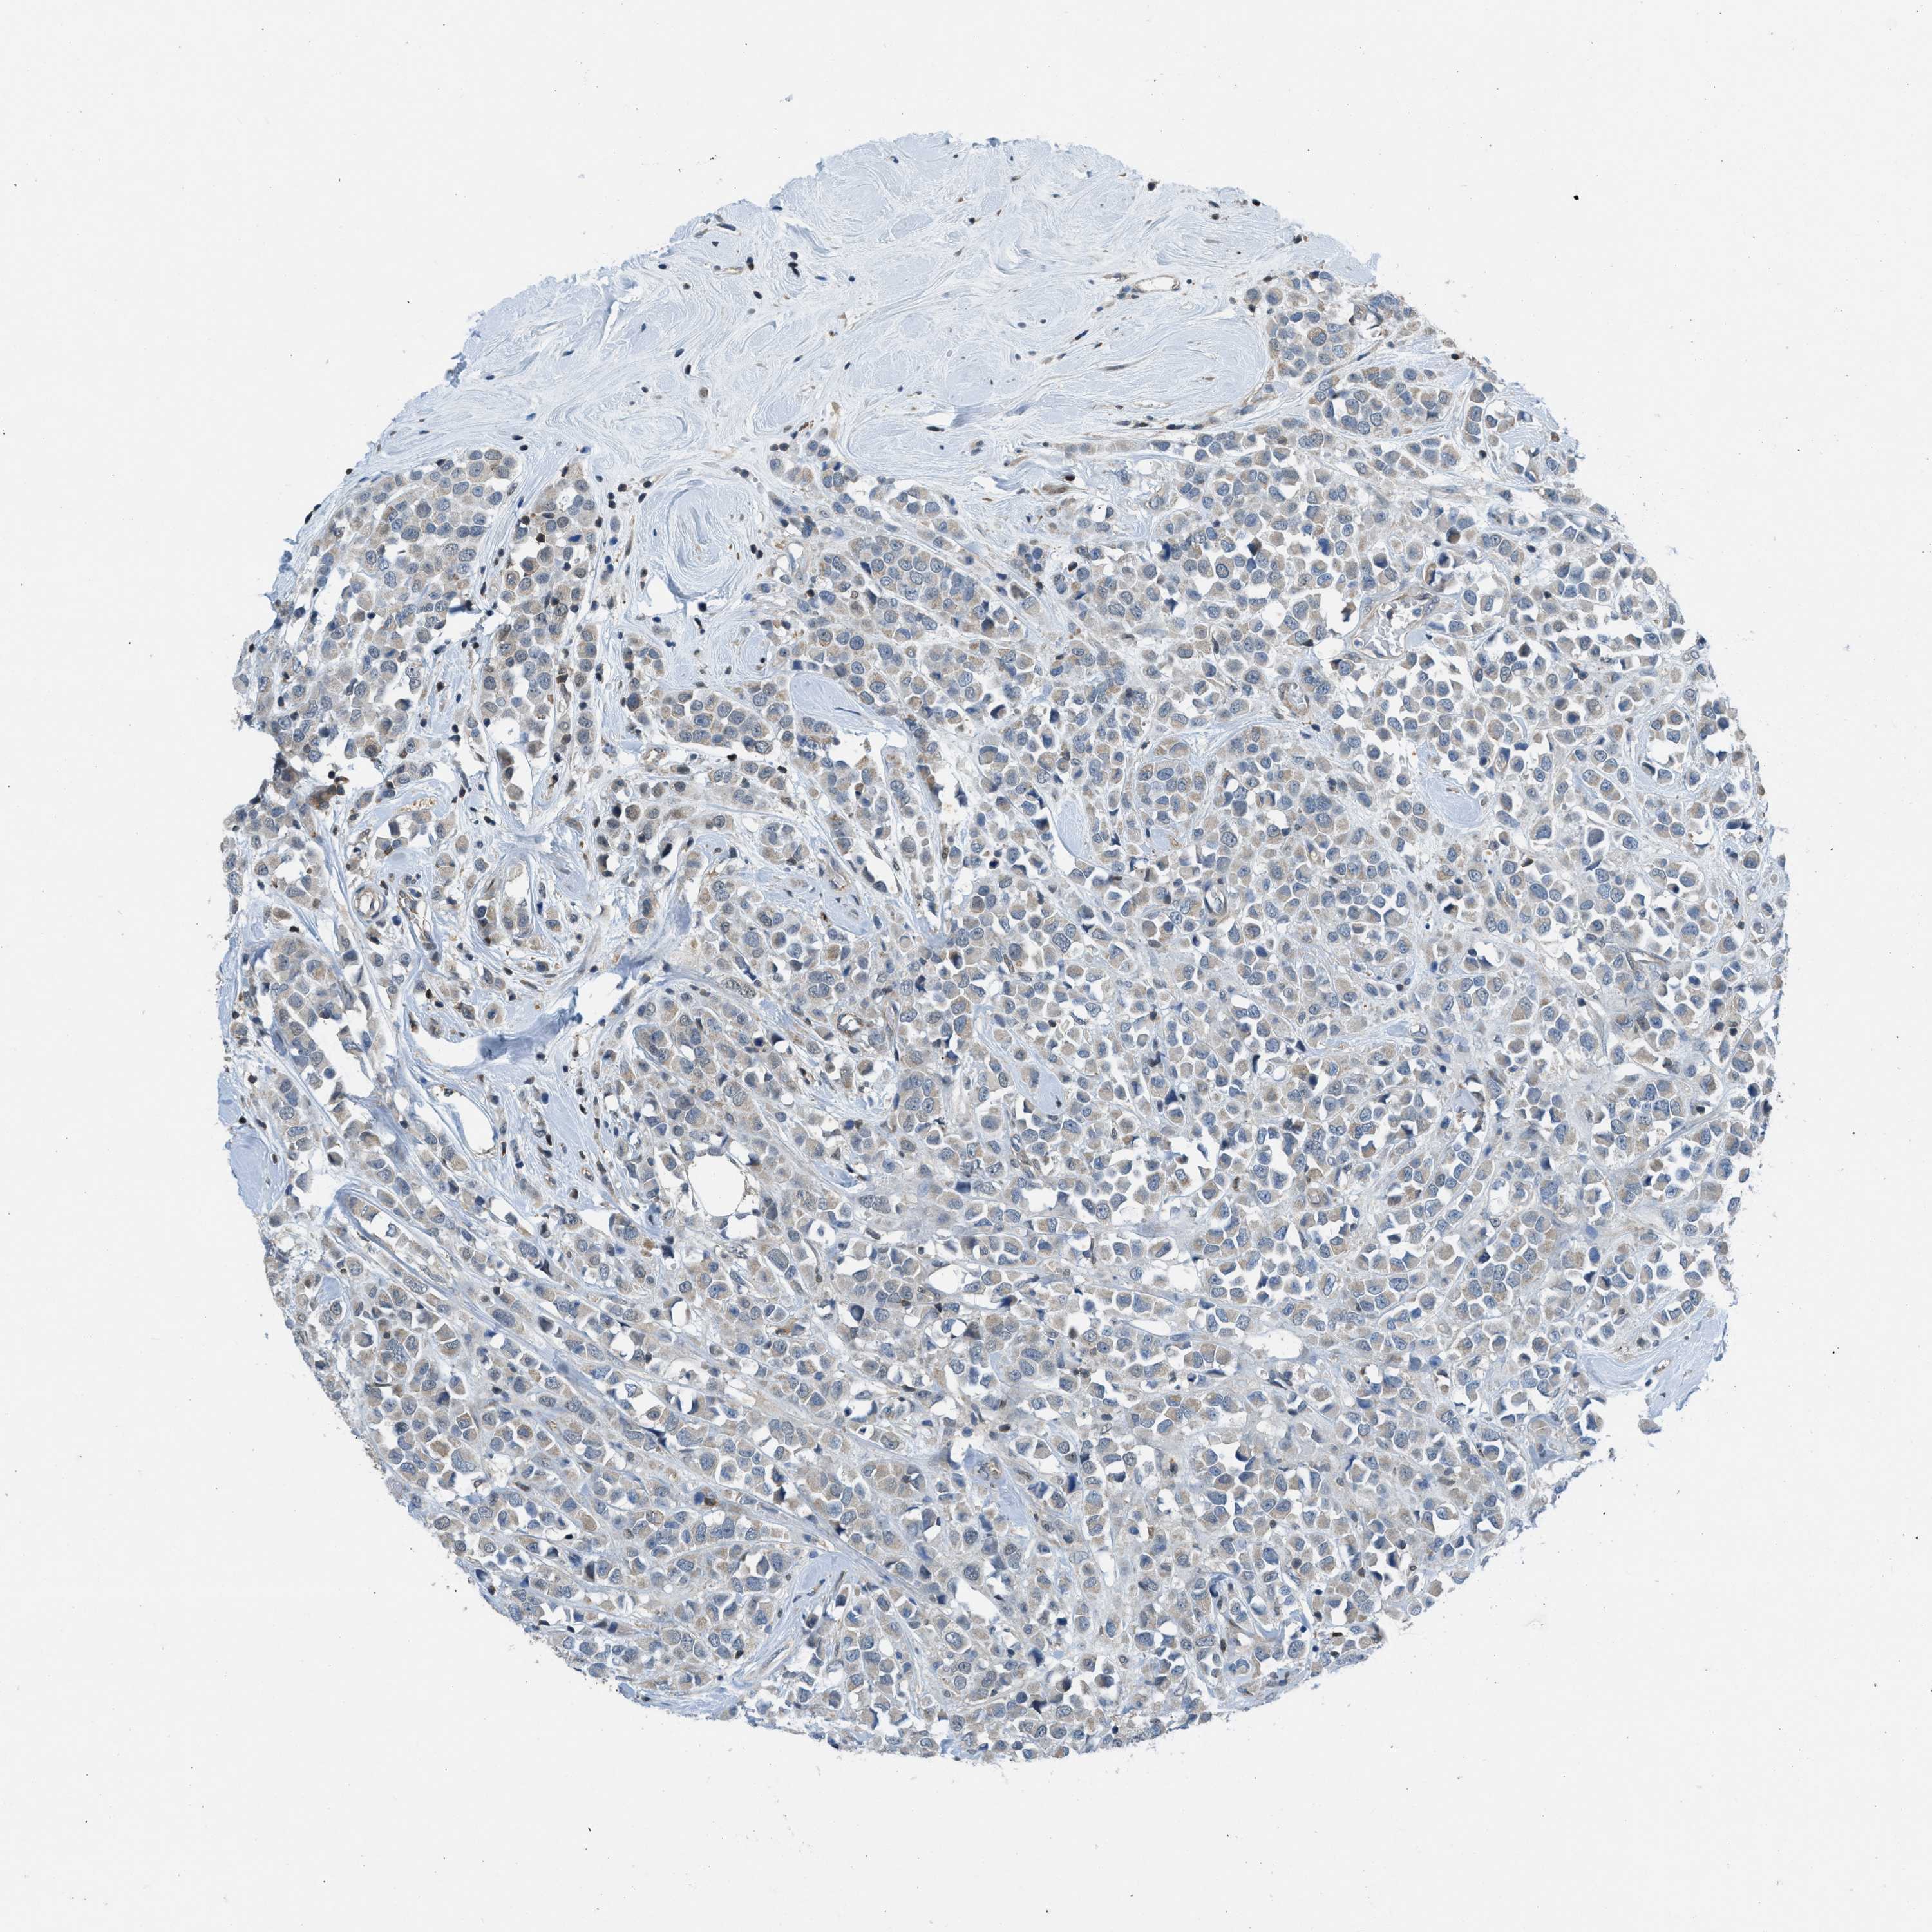

CANCER BREAST CANCER Show tissue menu

BRCA TCGA BRCA VALIDATION PROTEIN EXPRESSION